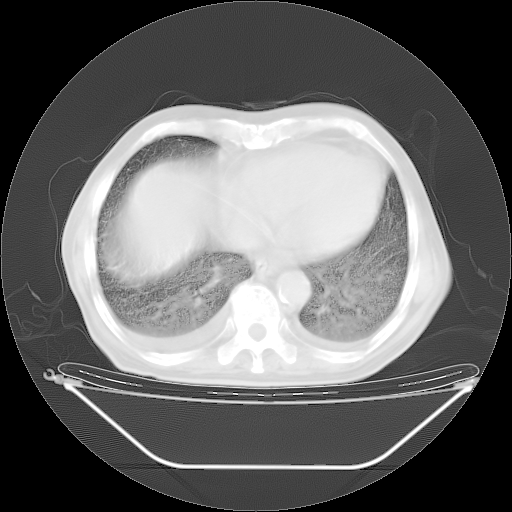

今天复查肺部CT,发现双肺广泛磨玻璃样改变。所以我把3月19日和5月9日相隔50天的肺部CT上传。请大家会诊。

2009年3月19日肺部CT片。

2009年3月19日肺部CT